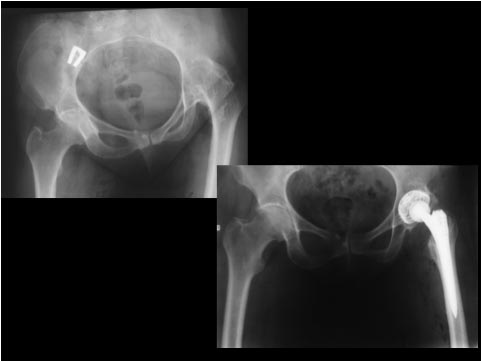

В прикреплённом файле очень похожее клиническое наблюдение. Пациентке на момент операции 59 лет. Прошло 4 года. На мой вопрос о спине, которая болела перед операцией, она по телефону ответила: А причём тут спина, вы же мне ногу лечили, а спина меня уже не беспокоит. Восстановление функции сустава произошло в течении 6 месяцев. На днях обещала подойти, если так, представлю более демонстративную видеоинформацию. С уважением В.Б.Абдуев